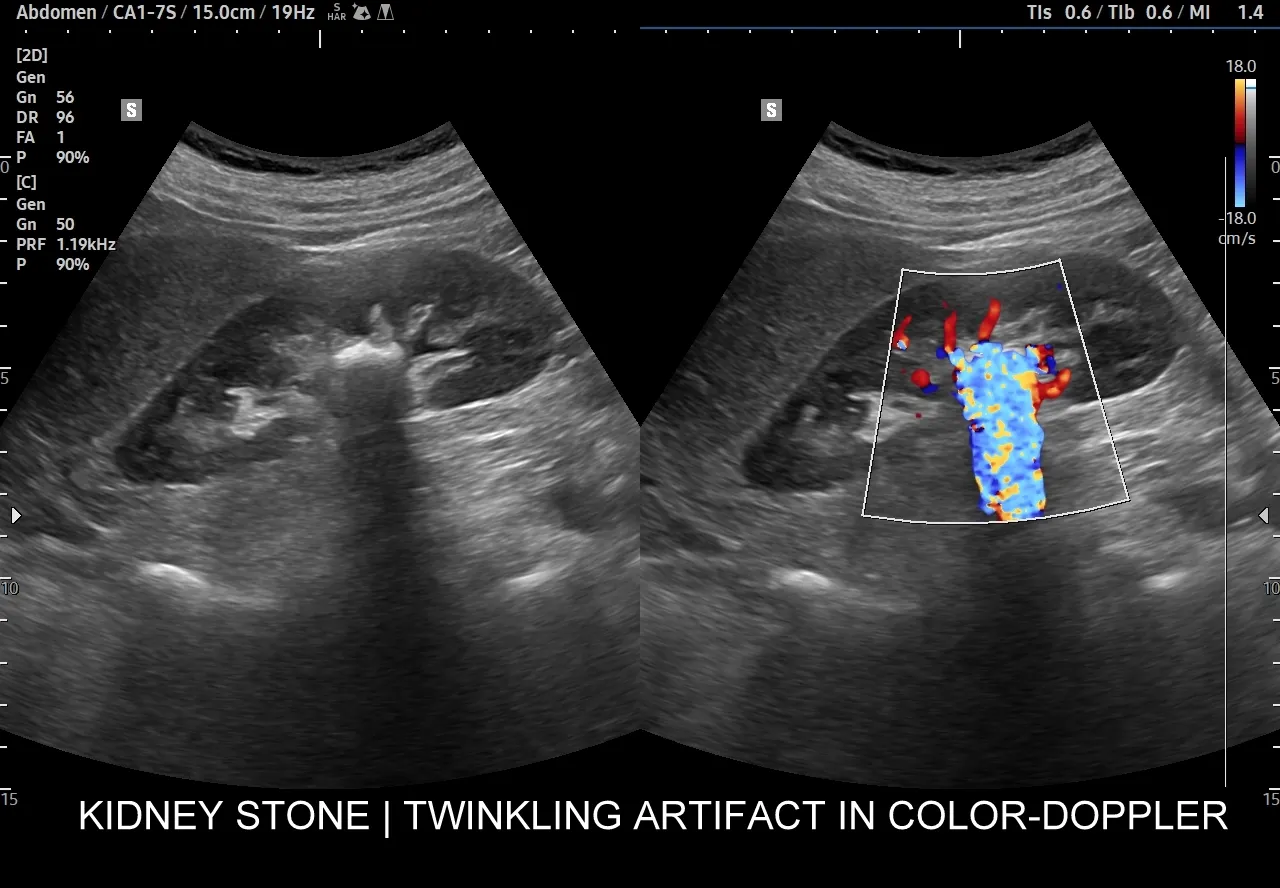

USG układu moczowego jest zazwyczaj pierwszym badaniem obrazowym, które zleca się przy podejrzeniu kamicy nerkowej, szczególnie w przypadku kolki nerkowej. To badanie jest szybkie, nieinwazyjne i całkowicie bezpieczne, ponieważ nie wykorzystuje promieniowania jonizującego. Dzięki temu jest preferowaną metodą diagnostyczną u dzieci i kobiet w ciąży. USG pozwala na uwidocznienie kamieni o wielkości powyżej 3-4 mm, określenie ich lokalizacji w nerkach i górnych drogach moczowych, a co najważniejsze sprawdzenie, czy nie doszło do zastoju moczu, czyli wodonercza. Wodonercze jest sygnałem, że kamień blokuje odpływ moczu, co wymaga szybkiej interwencji.

Kiedy potrzebujemy absolutnej precyzji, wkracza niskodawkowa tomografia komputerowa bez kontrastu (CT KUB). Jest ona obecnie uznawana za "złoty standard" w diagnostyce kamicy nerkowej. Jej czułość wynosi aż 95-100%, co oznacza, że jest w stanie wykryć niemal wszystkie typy kamieni, niezależnie od ich składu chemicznego nawet te, które są niewidoczne w RTG. TK precyzyjnie określa wielkość i położenie kamienia, co jest kluczowe przy planowaniu leczenia, zwłaszcza zabiegowego. Zleca się ją, gdy wynik USG jest niejednoznaczny, gdy kamień jest mały lub trudno dostępny, a także przed każdą interwencją urologiczną, aby mieć pełen obraz sytuacji.

Jak widać, choć USG jest świetne do szybkiej oceny i wykrywania wodonercza, TK oferuje niezrównaną precyzję, zwłaszcza gdy chodzi o małe kamienie, kamienie w moczowodach czy te o nietypowym składzie chemicznym, które mogą być niewidoczne w USG.